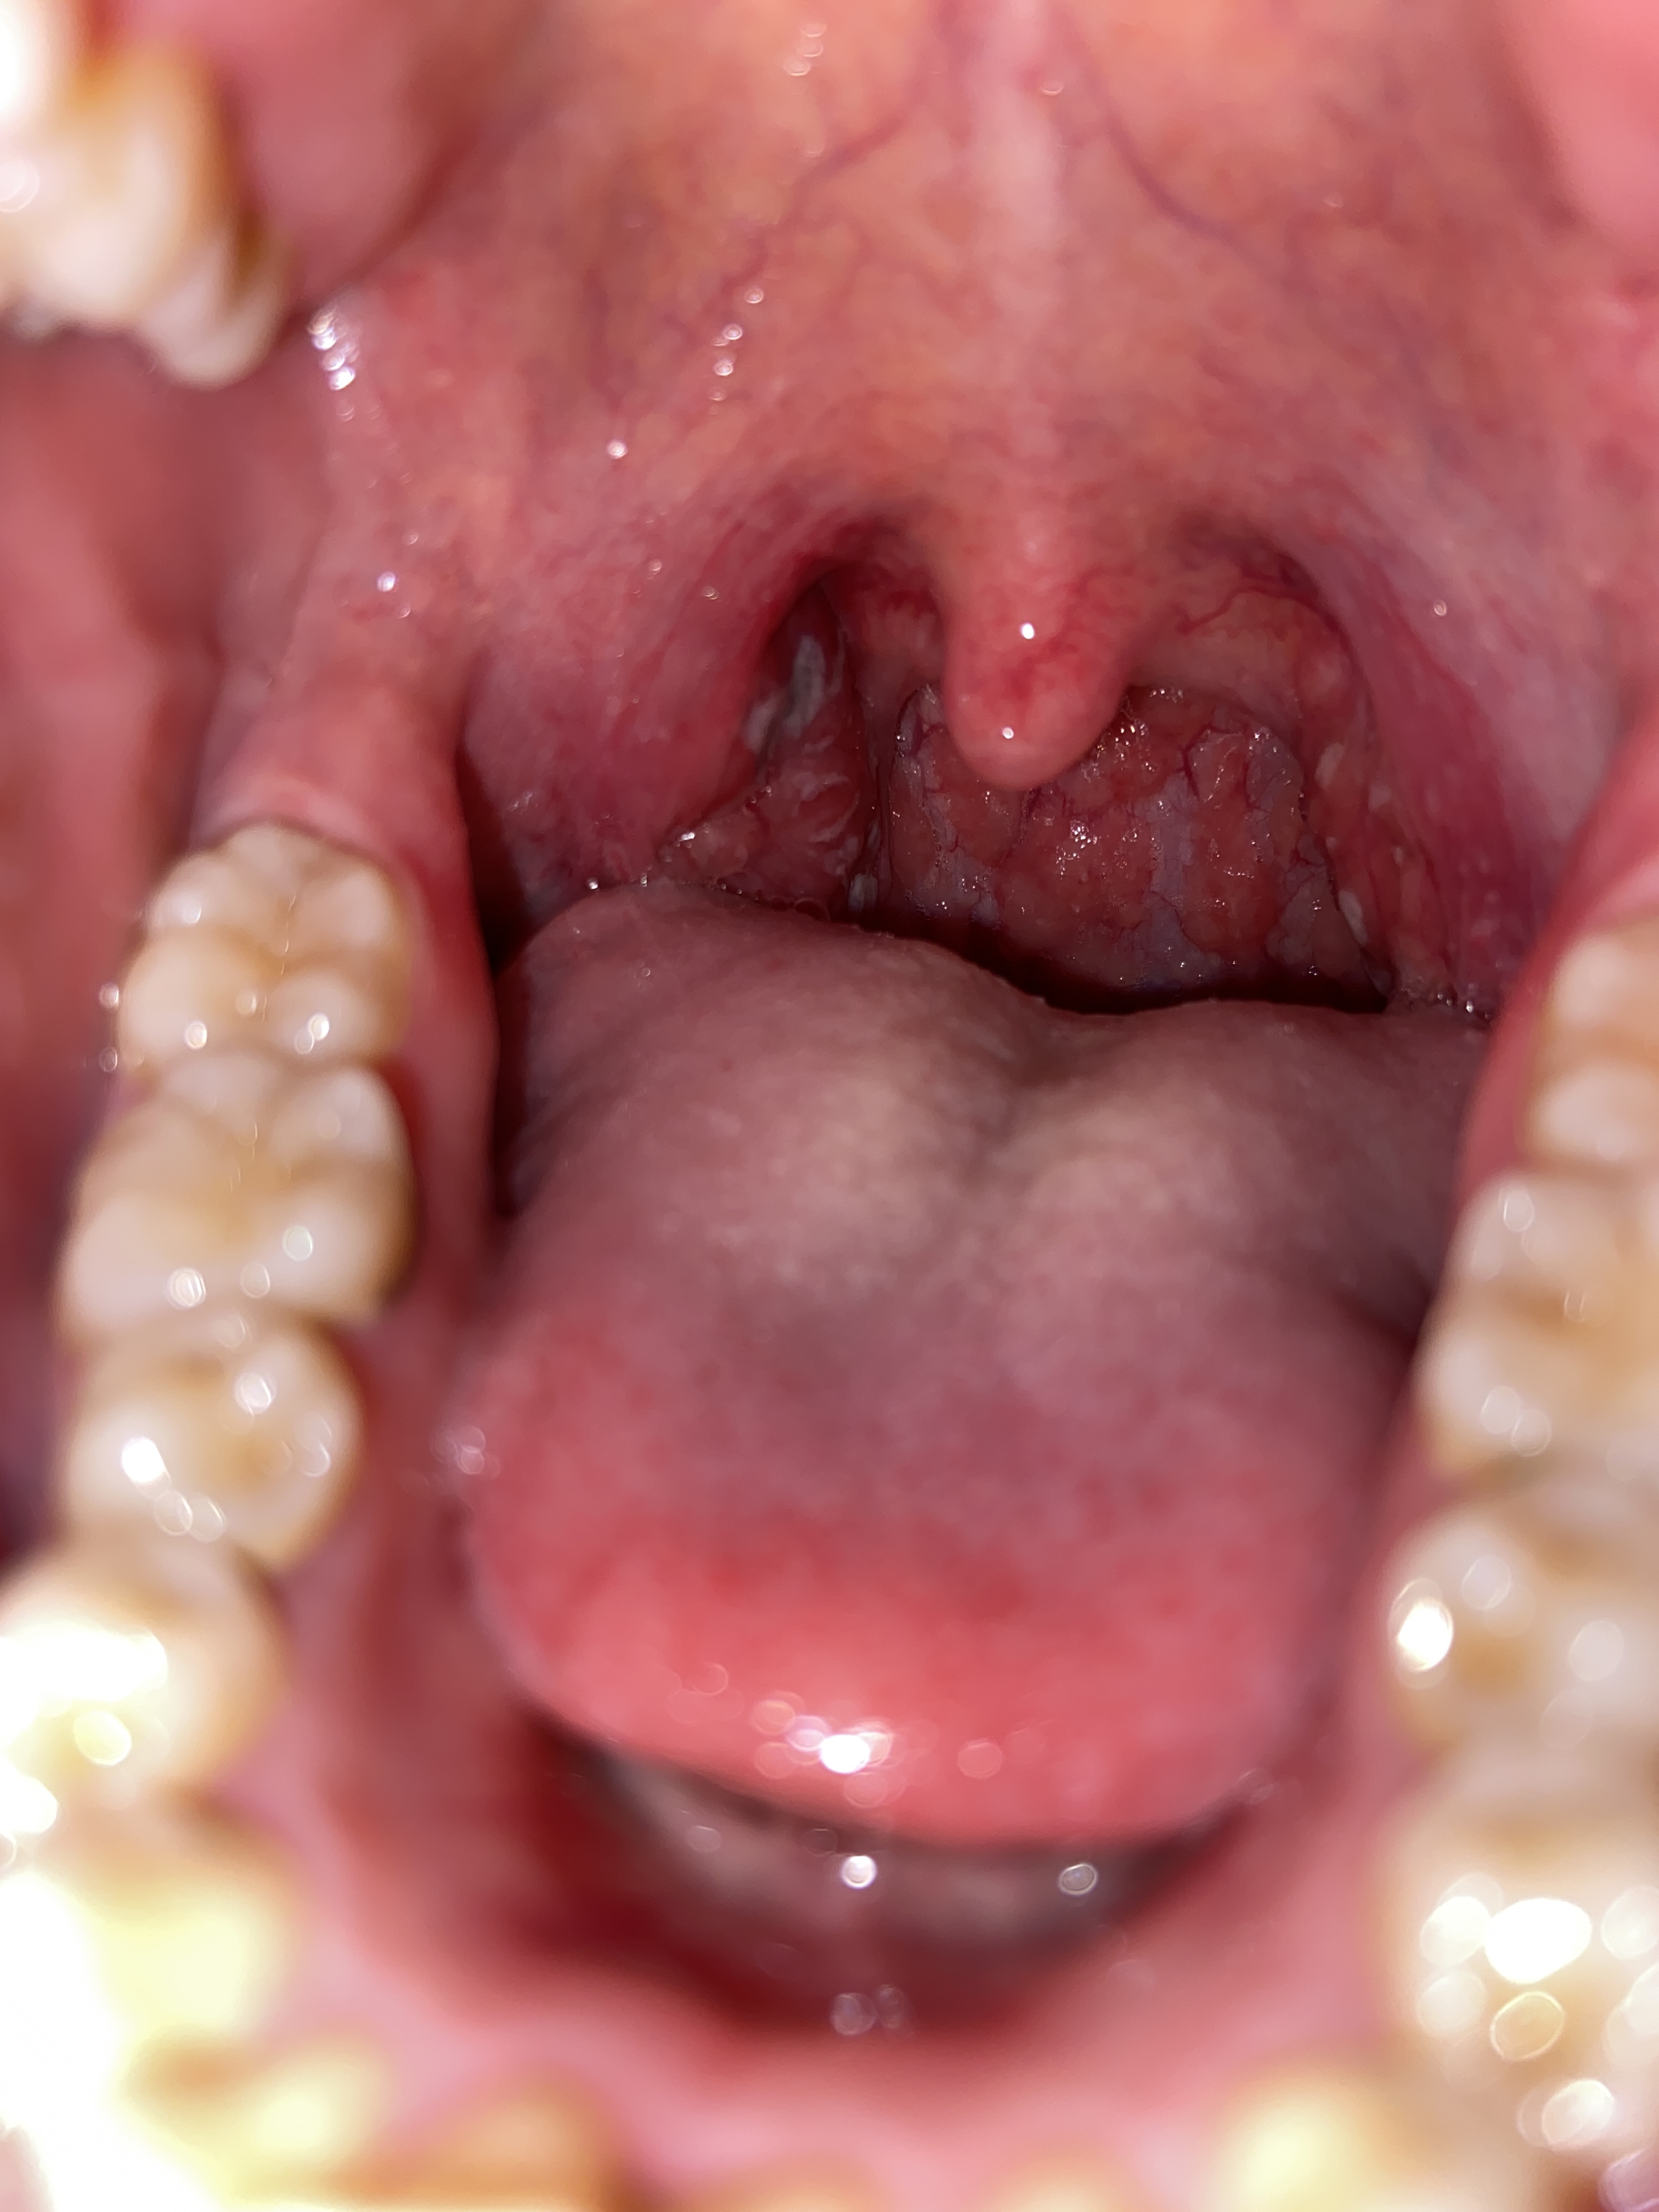

Bác sĩ ơi em đau họng xuất hiện mủ trắng.đi khám hồi sáng kết luận viêm amidan có mủ. Giờ soi đèn thấy mủ chuyển sang màu đen như này là sao ạ

Hình ảnh amydal hốc mủ. Vị trí đó em kiểm tra có hiện tượng vỡ mủ không